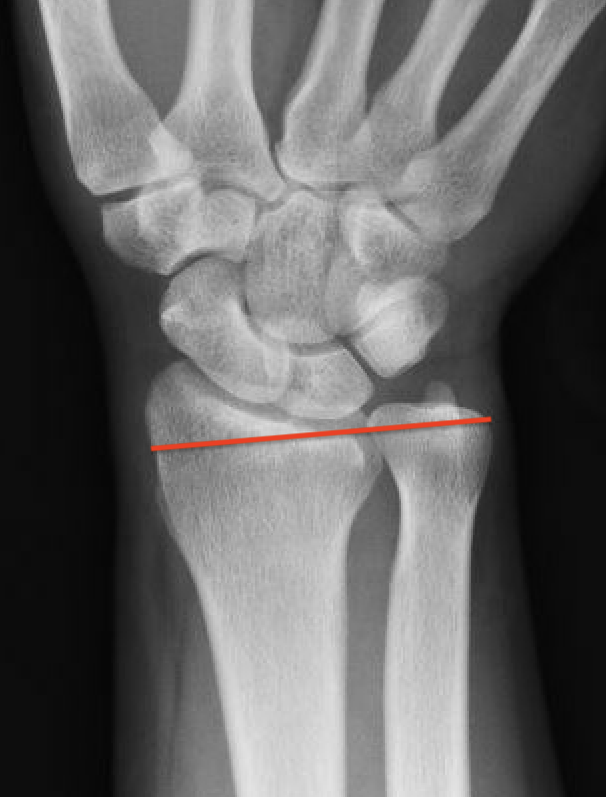

Ulna positive

Class 2 Degenerative TFCC tears

Central TFCC tear with ulna positive variance an ulnocarpal abutment on MRI

Background

Ulna impaction syndrome / Ulno-carpal abutment

Progression of wear

- TFCC thinning

- ulna head and lunate cartilage wear

- TFCC perforation

- lunate-triquetral ligament injury

- ulnocarpal osteoarthritis

Usually associated with ulna positive variance and treated with ulna shortening